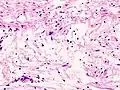

C'est un sous-type exceptionnel des schwannomes. Il s'agit d'une tumeur nerveuse bénigne, dont le point de départ est la gaine de Schwann. C'est souvent un nodule solitaire, asymptomatique, siégeant dans le tissu cutané ou sous-cutané, et dont la taille augmente progressivement.

Schwannome mélanotique

C'est une tumeur rare. Elle s'intègre, dans 50 % des cas, dans le complexe de Carney (myxomes cardiaques, pigmentation lentigineuse faciale, anomalies endocriniennes). Il existe au sein de la prolifération d’abondantes mottes de mélanine ainsi que des psammomes (en). Les cellules tumorales expriment la PS100 et l’HMB45 (marqueur de différenciation mélanocytaire).